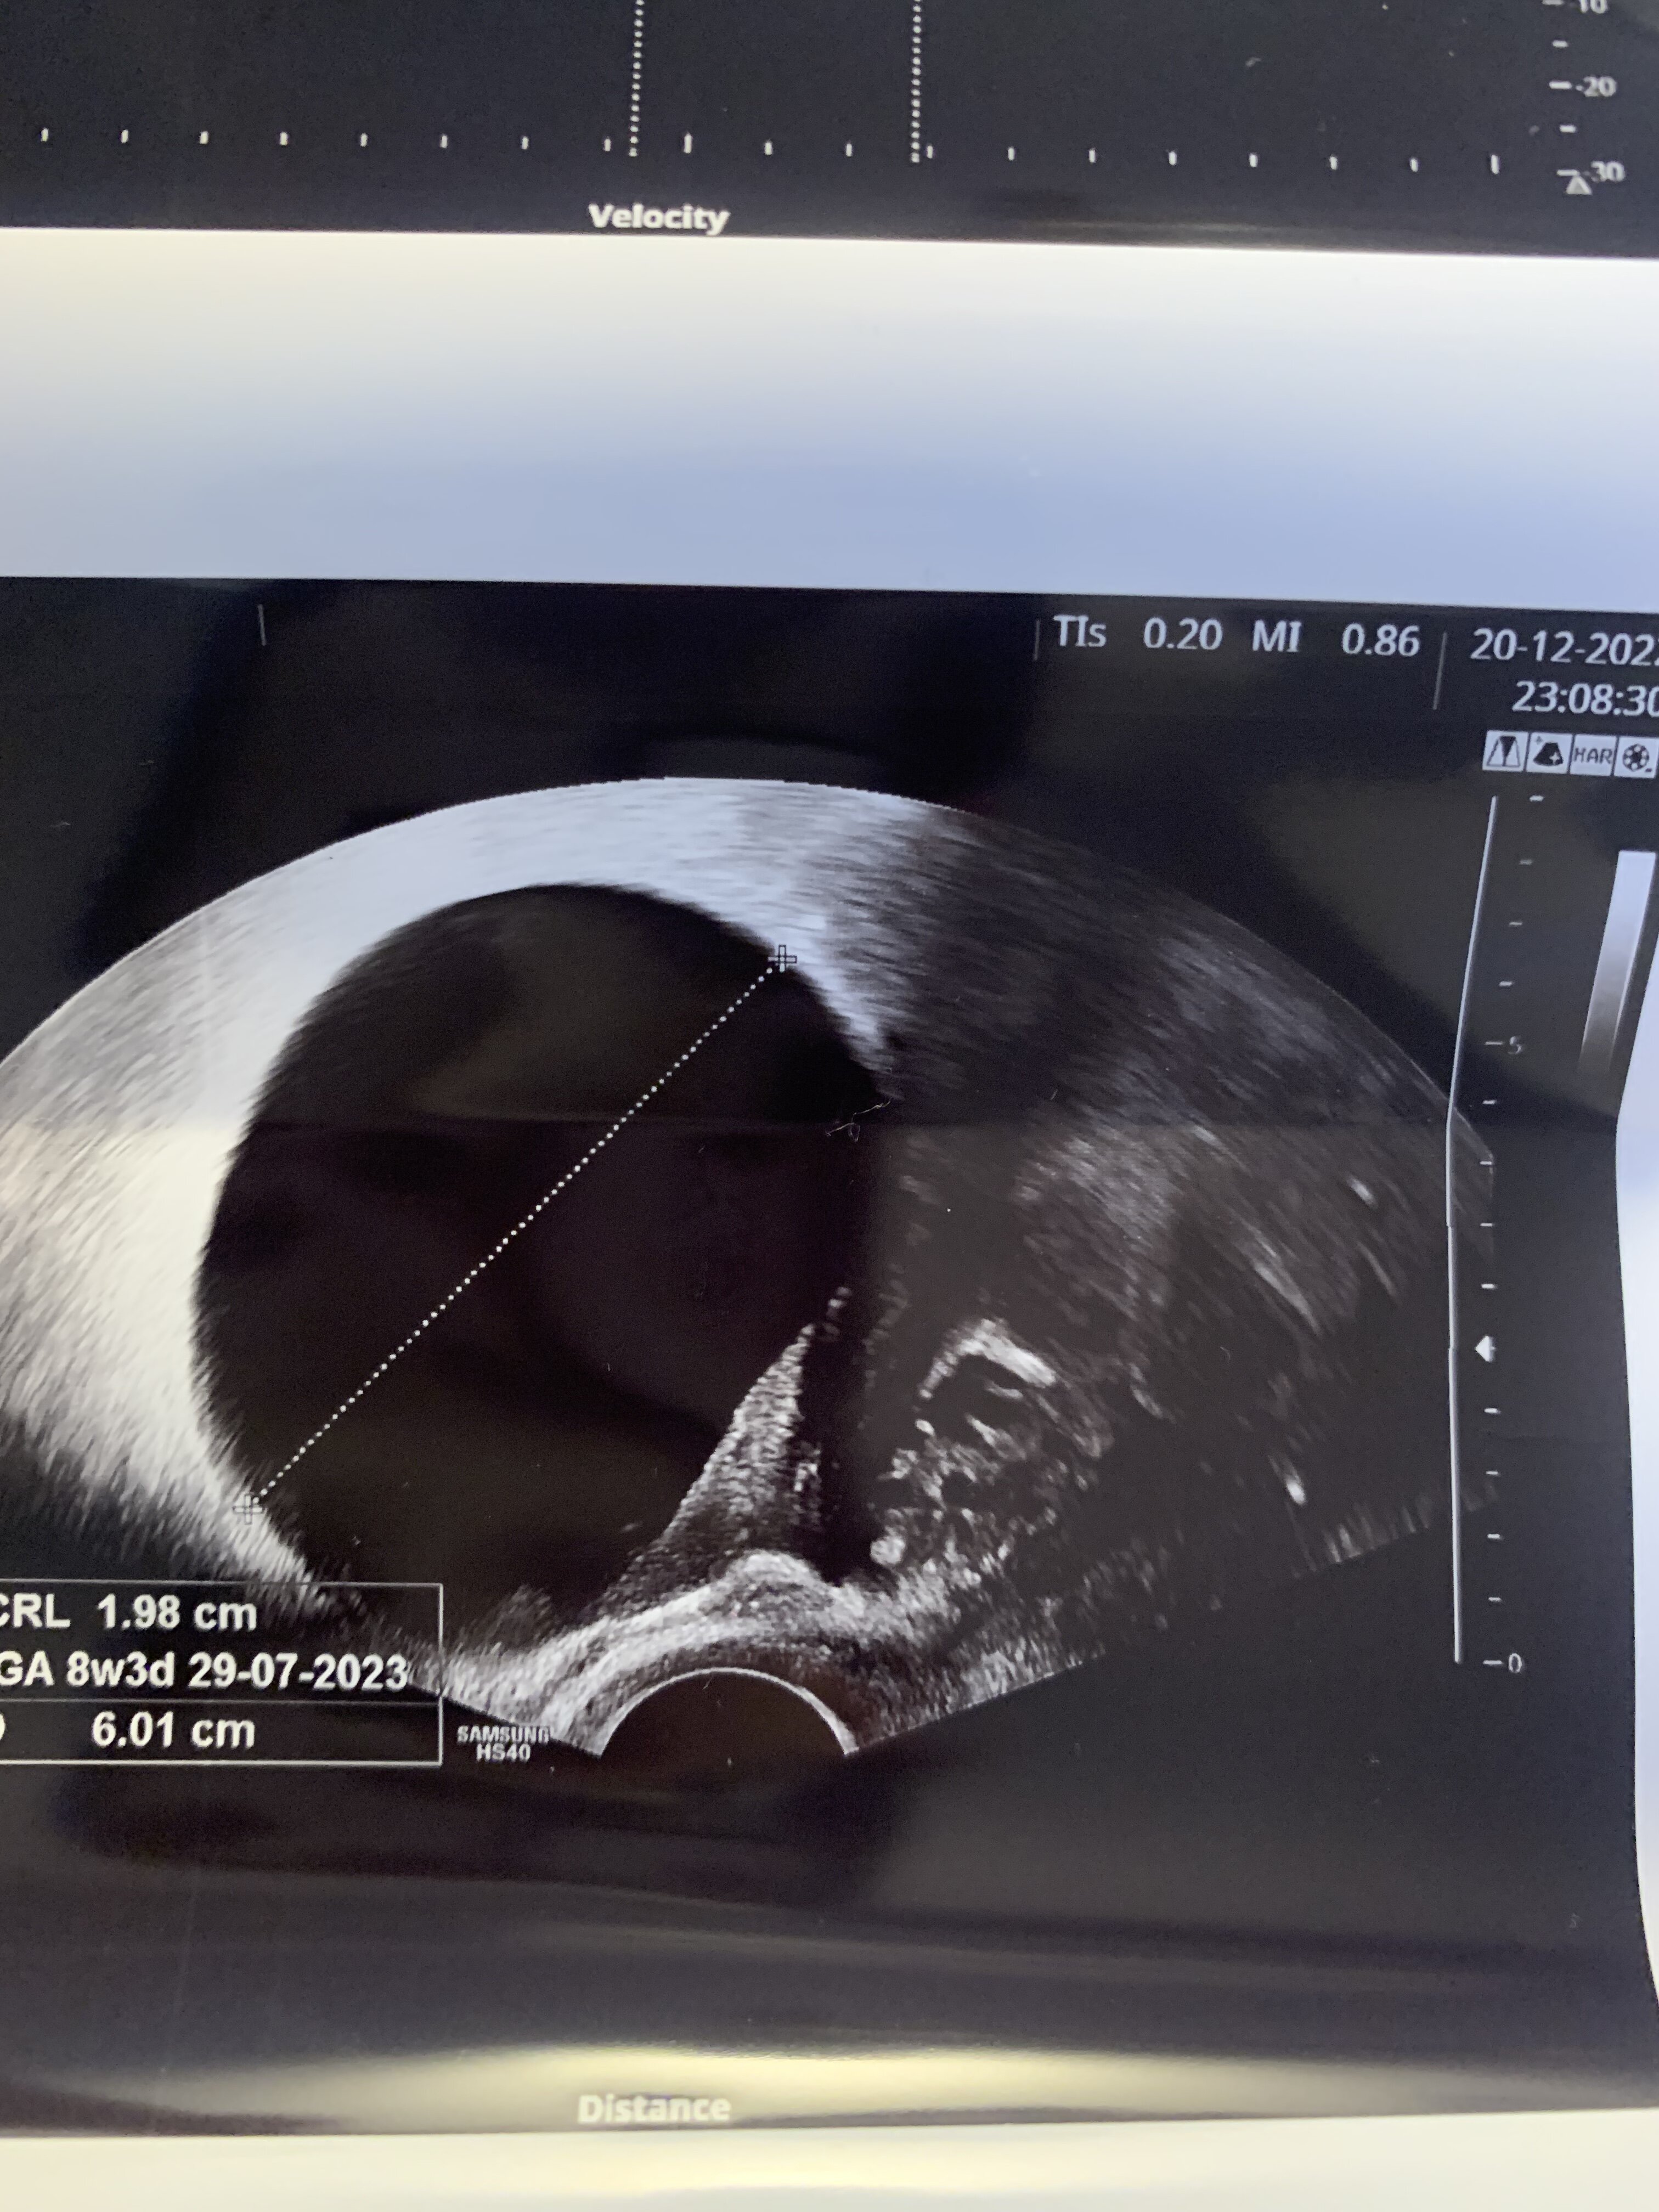

Witam po długiej przerwie. Uporaliśmy się z wirusem RSV. Dziecko dzisiaj poszło do żłobka a ja do pracy. Dzisiaj mam 10 tydzień +1 i mam takie pytanie czy któraś z was miała w poprzedniej ciąży lub ma teraz torbiel czynnościową? Kiedy to dziadostwo się wchłonie? Odczuwam dyskomfort podczas długiego siedzenia lub leżenia na boku. Zastanawiam się jak długo to potrwa 😕 takie mam zdjęcia jak był 8 tydzień +2

• 02FB470F-98AA-446E-86EB-B56A7419E1D8.jpeg

02FB470F-98AA-446E-86EB-B56A7419E1D8.jpeg

1,3 MB · Wyświetleń: 85